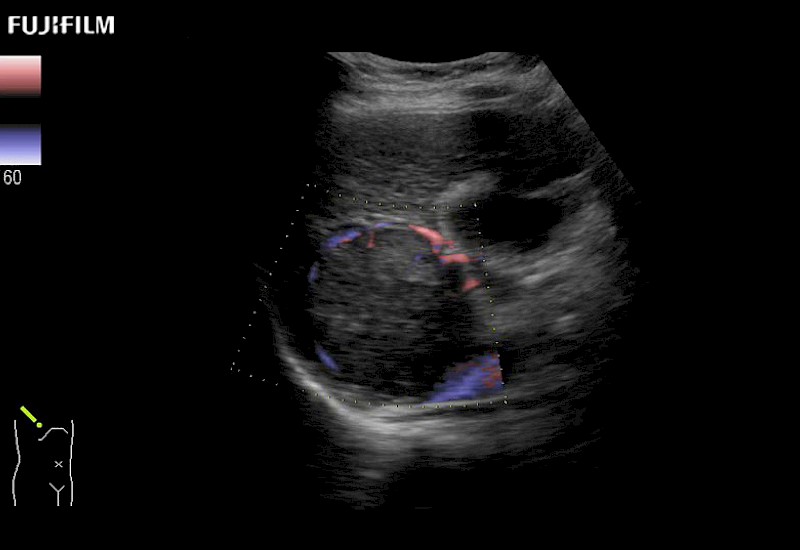

Extraordinary high-resolution digital imaging

Exceptional transducers

for use during open and laparoscopic procedures: Tumor localization & staging, Ablation, Resection, Biopsy, Transplant, Abdominal exploration, Robotic surgery

Multi-Parametric imaging modalities